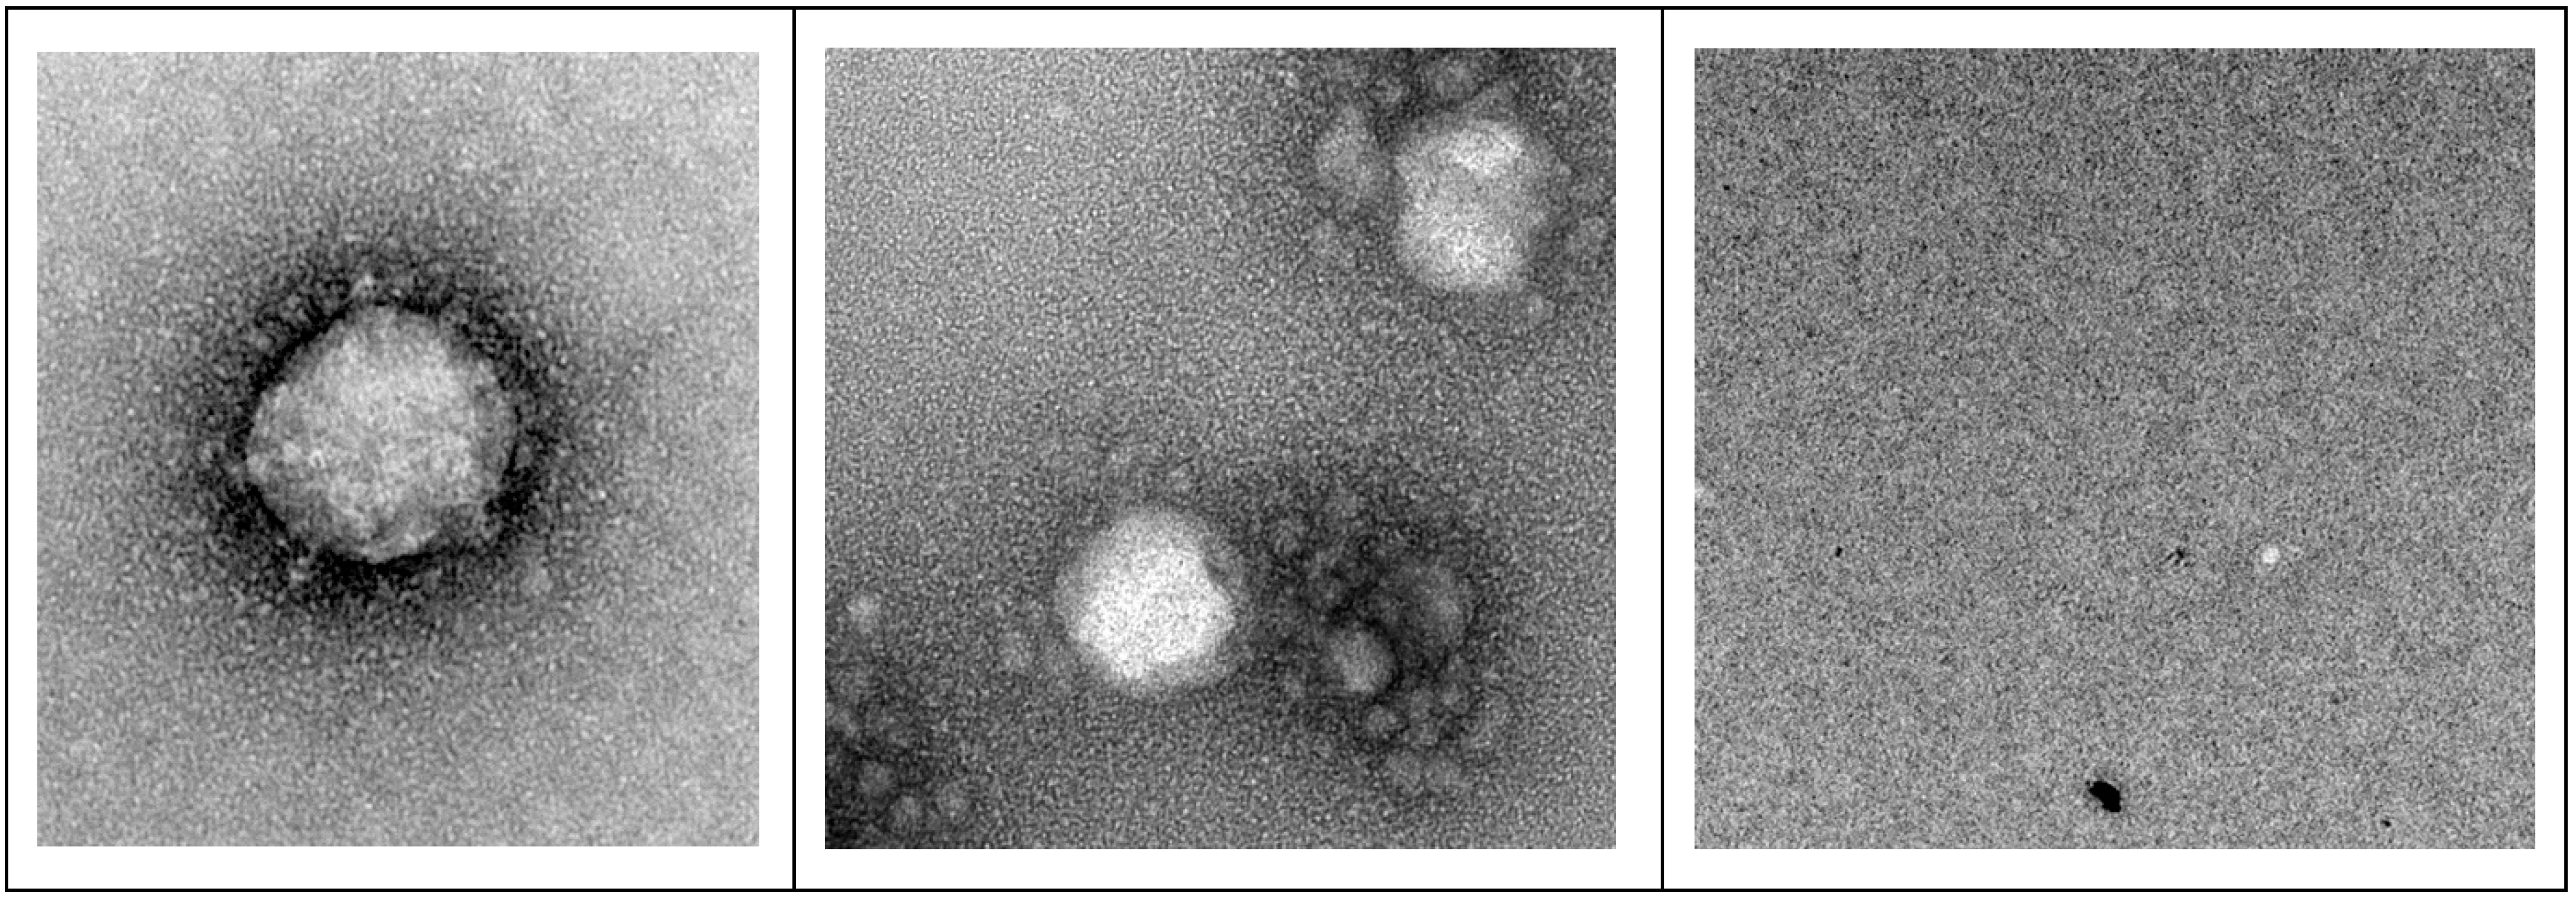

3.3. Transmission Electron Microscopy (TEM) Imaging of F18D-Treated Virus